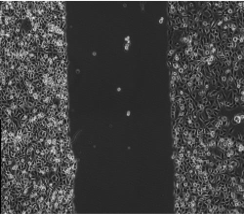

原代(dài)細胞(bāo):原代培養是直接從(cóng)生物體獲取組織或器官的一部分進(jìn)行培養。原代培養細胞與(yǔ)體內原組織在形態(tài)結構和功(gōng)能活動上(shàng)相似性大。由於培養的細(xì)胞剛(gāng)剛從活體組織分離出(chū)來(lái),故更接近於生物體內的生活狀態。這一方法可為研究生物體細胞的(de)生長、代(dài)謝、繁殖提供有力的手(shǒu)段。

腫瘤細胞:腫瘤細(xì)胞在組織培(péi)養中占有(yǒu)核心的位置,首先癌細胞是比較容易培養的細胞。當前建立的細(xì)胞係中(zhōng)癌(ái)細胞係是最多的(de)。腫(zhǒng)瘤細(xì)胞培養是研究(jiū)癌變機理、抗(kàng)癌藥(yào)檢測、癌分子(zǐ)生物學極其重要的(de)手段。腫瘤(liú)細胞培養對闡明和解決癌症將起著不可估量的(de)作用。